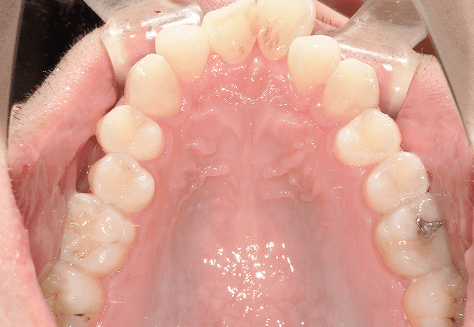

S.K

治療前

治療後

主訴

歯が重なっていて気になる。前歯が出ていて唇が閉じにくい。ハミガキがしにくい。

診断

上顎前突・叢生

年齢/性別

20代/男性

抜歯部位

上下第三大臼歯

使用装置

上下インビザライン

保定装置

上下ビベラリテーナー

診察料金

1,100円×33回

治療期間

3年5カ月